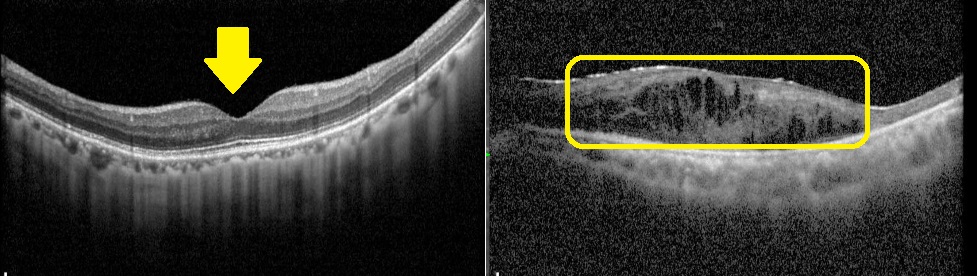

土城醫院院長賴旗俊為世界級眼科權威、知名視網膜專家,他指出黃斑部病變是台灣中老年人視力喪失的常見原因之一,尤其於50歲以上族群為主。黃斑部位於視網膜中央,是負責辨識細節、閱讀、認人及觀看影像的關鍵區域,一旦出現病變,將嚴重影響生活品質。初期異常症狀常由單眼開始,出現閱讀跳字、字體扭曲、中央視野模糊或黑點等情況,但容易與老花眼或視覺疲勞混淆,延誤就醫時機。尤其是濕性老年性黃斑部病變,若延誤治療超過2年,高達9成以上患者視力會惡化至0.05以下,甚至可能造成失明。

黃斑部病變分為乾性與濕性兩類,乾性病變約佔8成,病程進展慢,目前無特效藥,只能靠改善生活習慣延緩惡化,如配戴太陽眼鏡防止強光照射、戒菸、控制三高、補充抗氧化營養素等;濕性病變惡化速度快,主要是由新生血管異常增生造成出血與水腫,需透過眼內玻璃體注射抗血管新生藥物治療。若符合健保給付標準,單眼最多可施打14劑眼內注射藥物,臨床顯示約8成患者連續注射3劑後,3個月內視力可改善;但若延誤治療,95%的濕性患者在2年內可能造成失明,因此及早診斷與介入治療至關重要。